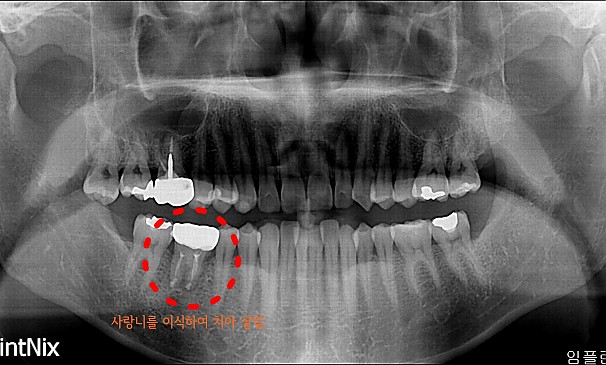

자가치아이식술

김OO님 전후사진 | 치료 기간 : 1주

치료 전